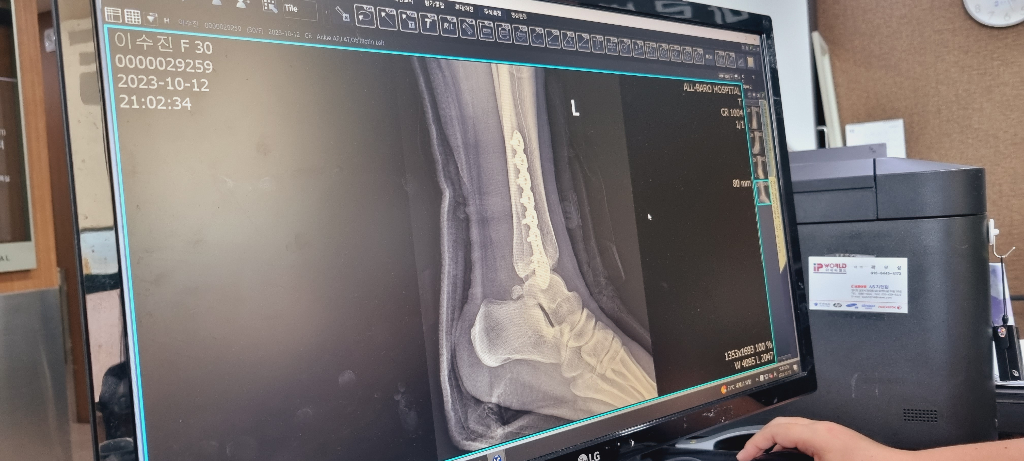

10월에 다리에 핀을박는 골절수술을 했습니다

수술경과는 좋지만 병원 수술비용이 너무 부담되서 다른병원에서 핀제거수술을받으려고하는데 가능할까요??

• 1번 째 사진